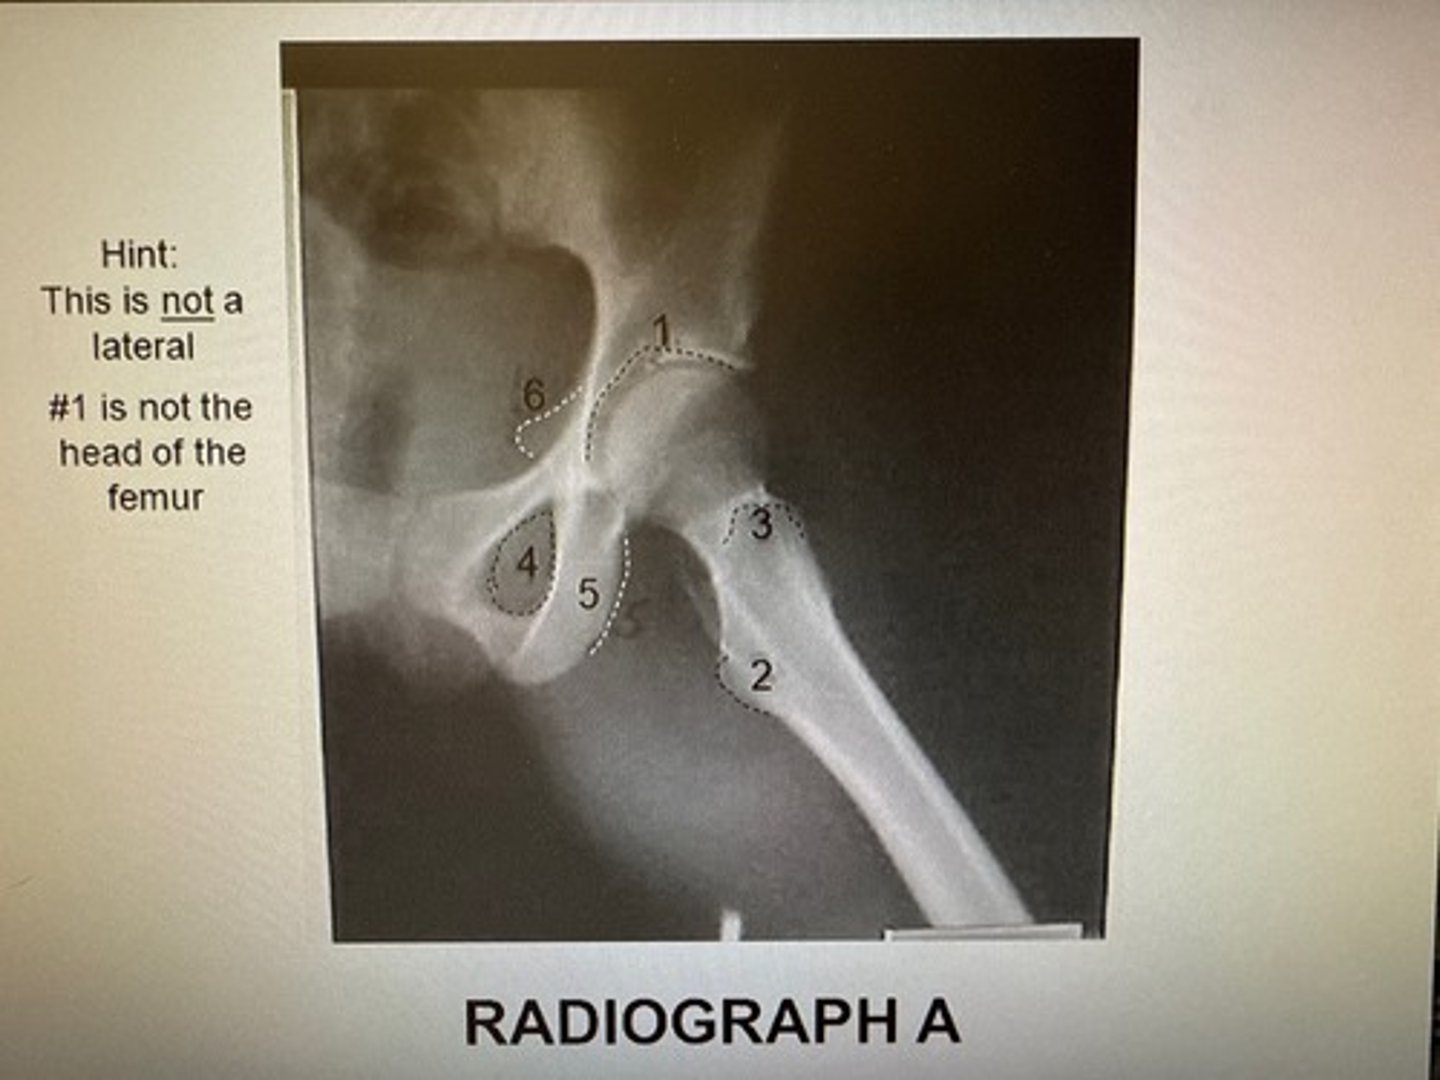

Identify the projection:

AP Hip

Axiolateral Hip (Danelius-Miller)

AP oblique hip (Modified Cleaves)

Lateral hip (Lauenstein)

Identify the anatomy marked A:

Pubis bone

Head of the femur

Femoral neck

Ischial tuberosity

Coccyx